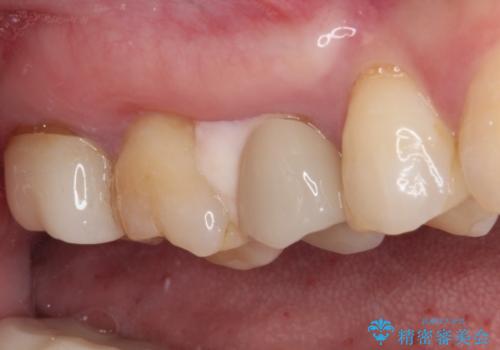

痛みが引いた後、不揃いな見た目で気になっていた左下の奥歯とともにオールセラミッククラウンにて補綴治療を行うこととしました。

将来ホワイトニングをされるとのことで、前歯よりもやや白い色合いのオールセラミッククラウンを選択されました。